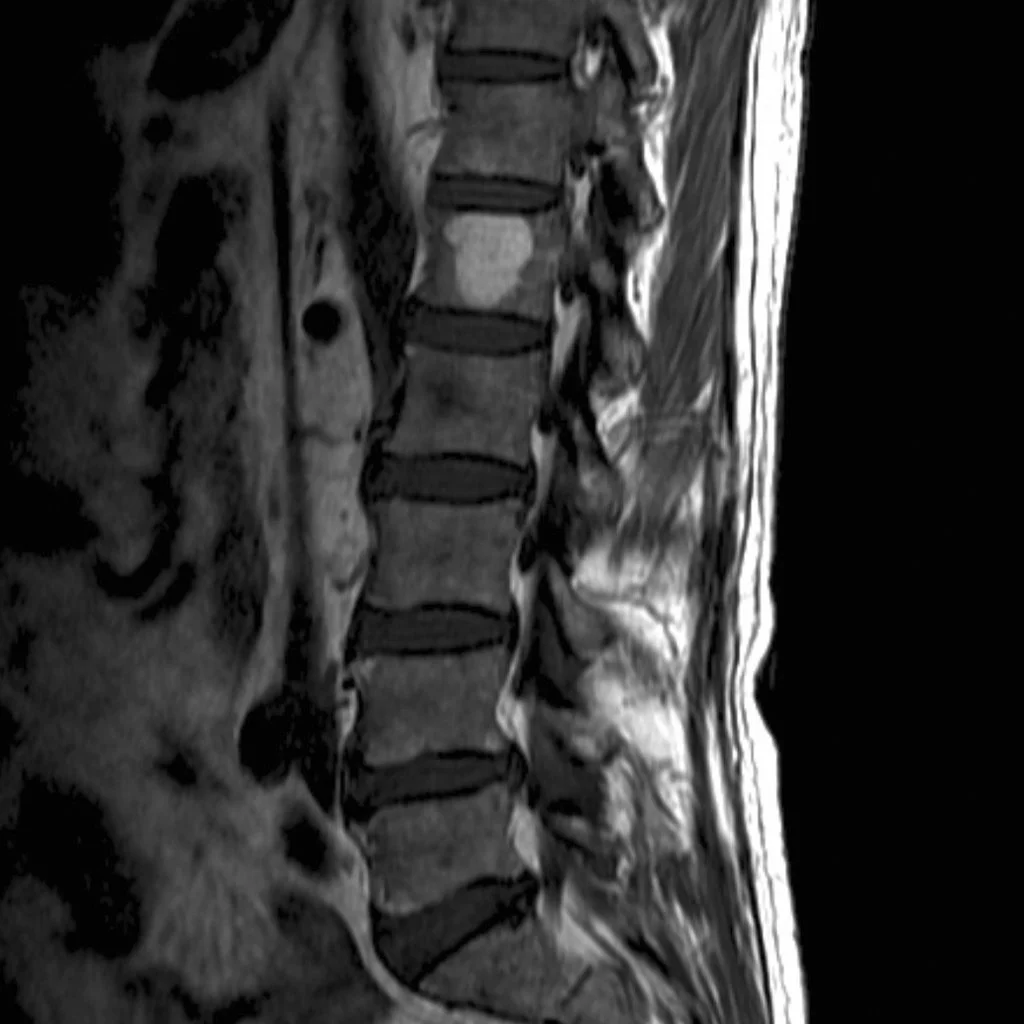

Professor Kate Stevens serves as a Professor of Radiology (Musculoskeletal Imaging) at Stanford Medicine, where she also directs the Ultrasound program within the MSK Imaging Division. Her clinical focus spans diagnostic radiology and musculoskeletal abnormalities, and she is deeply involved in advancing imaging education and research. As Director of Musculoskeletal Education since 2009, she has shaped training pathways and scholarly initiatives for radiologists at Stanford and beyond.